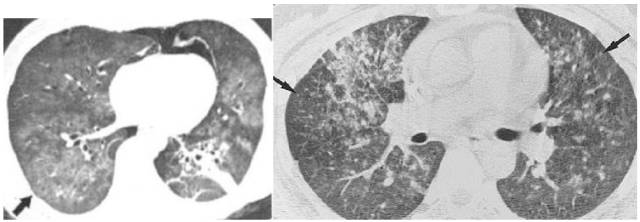

曲霉菌感染:树芽征+磨玻璃影+实变+空洞+结节+晕征+胸膜下楔形影+支气管壁增厚+菌球征 医学百科网 | YxBaike.Com

巨细胞病毒CMV:多发微结节+磨玻璃影+实变+小叶间隔增厚+纤维化+空气潴留 医学百科网 | YxBaike.Com